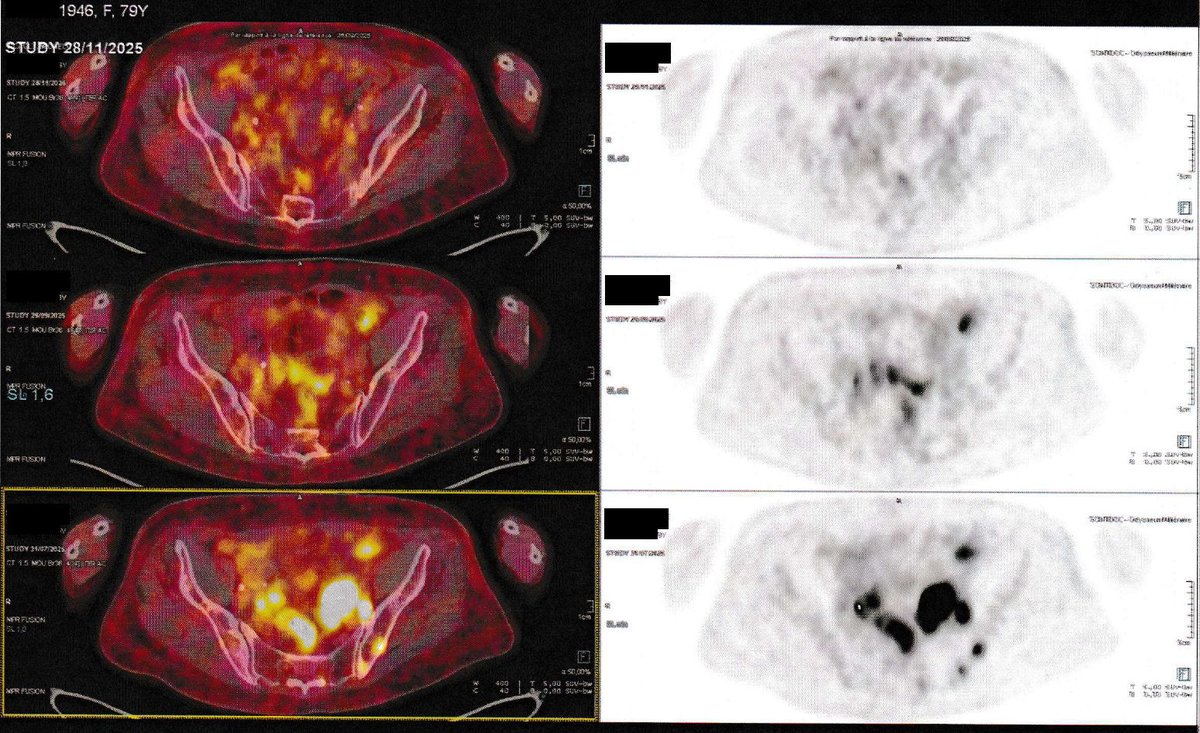

NEW ARTICLE: IVERMECTIN, MEBENDAZOLE, Vitamin B17, Graviola (Soursop) Testimonial - 79 year old woman in France with Stage 4 Ovarian Cancer achieves an impossible remission in 2 months! "Dear Dr. Zubin, I am writing to share some excellent news regarding the improvement of my